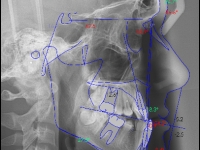

Paciente Clase III de 17 años

2014

El paciente D.M. llega a nuestra consulta sin los 2 premolares inferiores que le quitaron en anteriormente para empezar a mejorar el caso.

– Perfil plano

– Clase III esquelética

– Clase III dental

– Apiñamiento superior muy importante